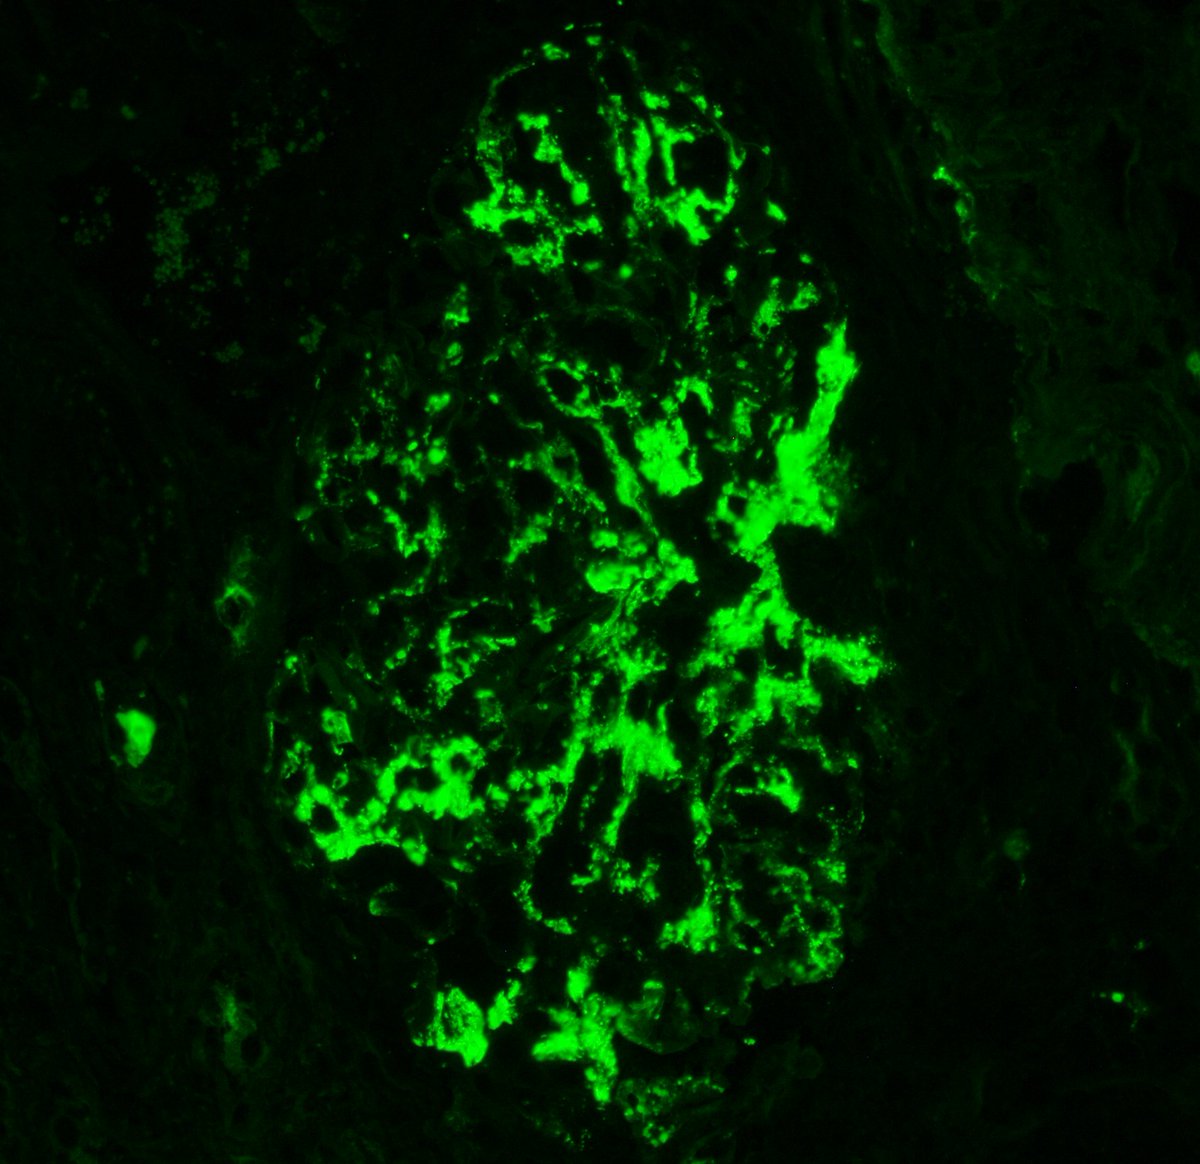

Diagnosis unmasked. Young F with 2g proteinuria, weak +dsDNA. Membranous pattern, IF with C3 dominant staining. Pronase IF --> IgG-k. Membranous-like glomerulopathy with masked monotypic IgG-k deposits. Considered to be autoimmune; not MGRS. #renalpath #pathtwitter #nephrology.

Typically occurs in young women with vague autoimmune history. Has not been associated with MGUS, plasma cell dyscrasias, or lymphomas. Deposits + for SAP. See references here: . https://t.co/CNa8qlPQkb https://t.co/qN4wxgDJp3